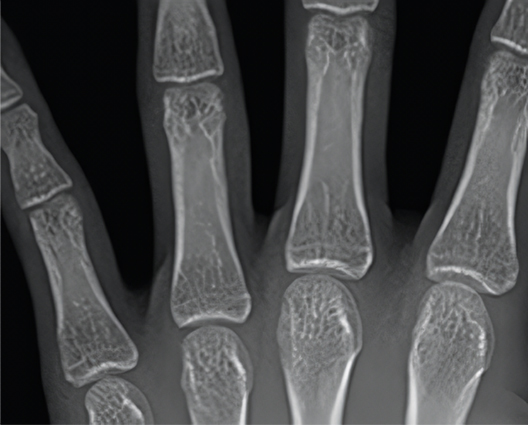

• Open Growth Plate